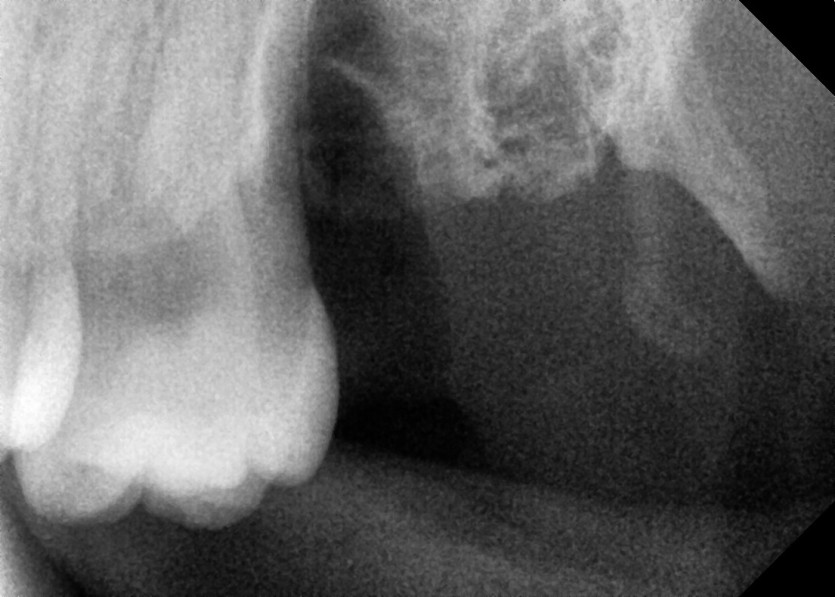

#28,38 사랑니 발치

구강외과 전문의가 당일 발치했습니다.